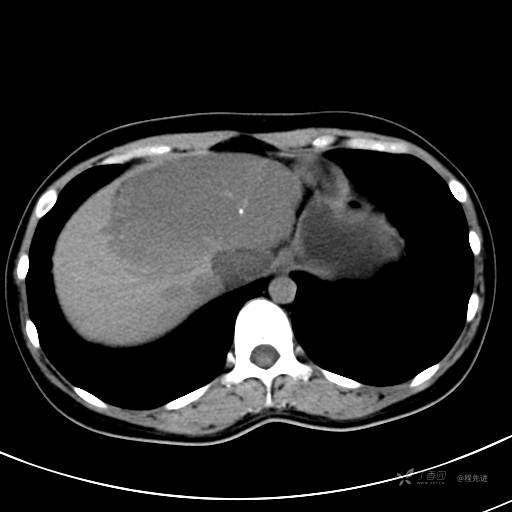

CT平扫+增强,每个序列3张图

CT值 平扫48HU 动脉期66HU 静脉期68HU 延迟期62HU